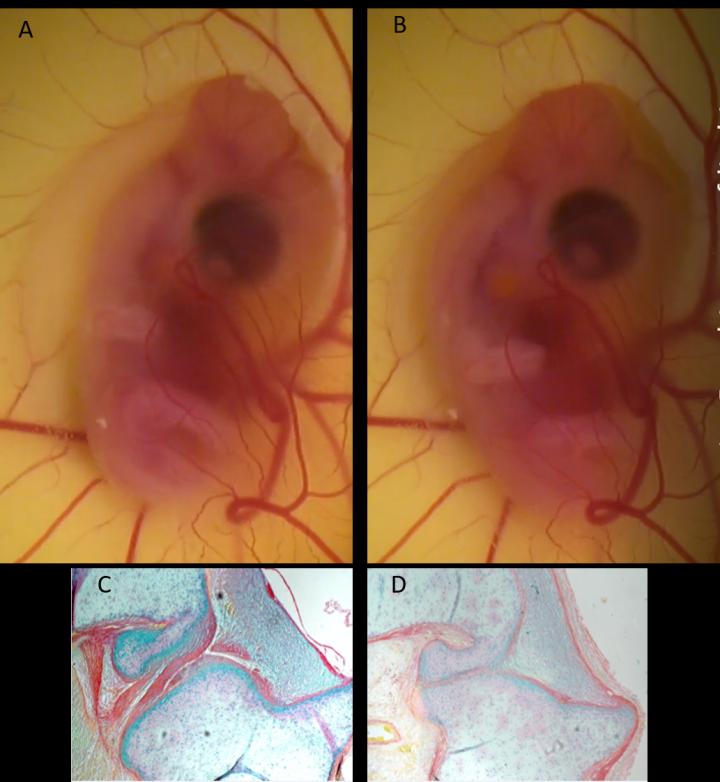

The researchers' discovery was made using chicken embryos, which develop similarly to their human equivalents and which can be easily viewed as development takes place - raising hopes that the finding may also apply to humans and thus have important implications for therapeutic interventions.

In the new study the researchers asked what happens if movement resumes after a defined period of movement restriction early in development. They specifically addressed whether joint and spine formation can recover.

"We compared resumption of normal movement to hyperactive movement and found that limb joints recover better than spinal defects and, among specific limb joints, those of the hips and knees recover best under the conditions tested.